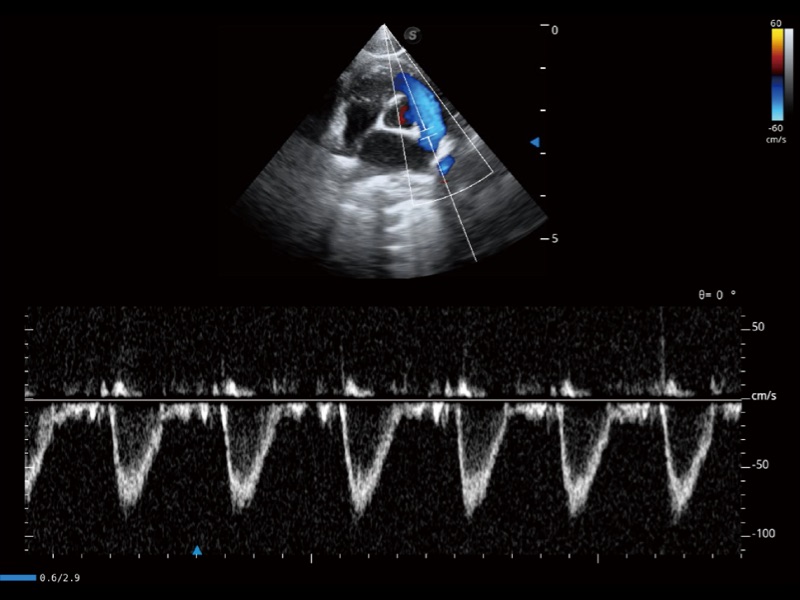

(猫)肺动脉血流频谱

(犬)左室长轴血流

(犬)四腔心

(犬)四腔心MQA